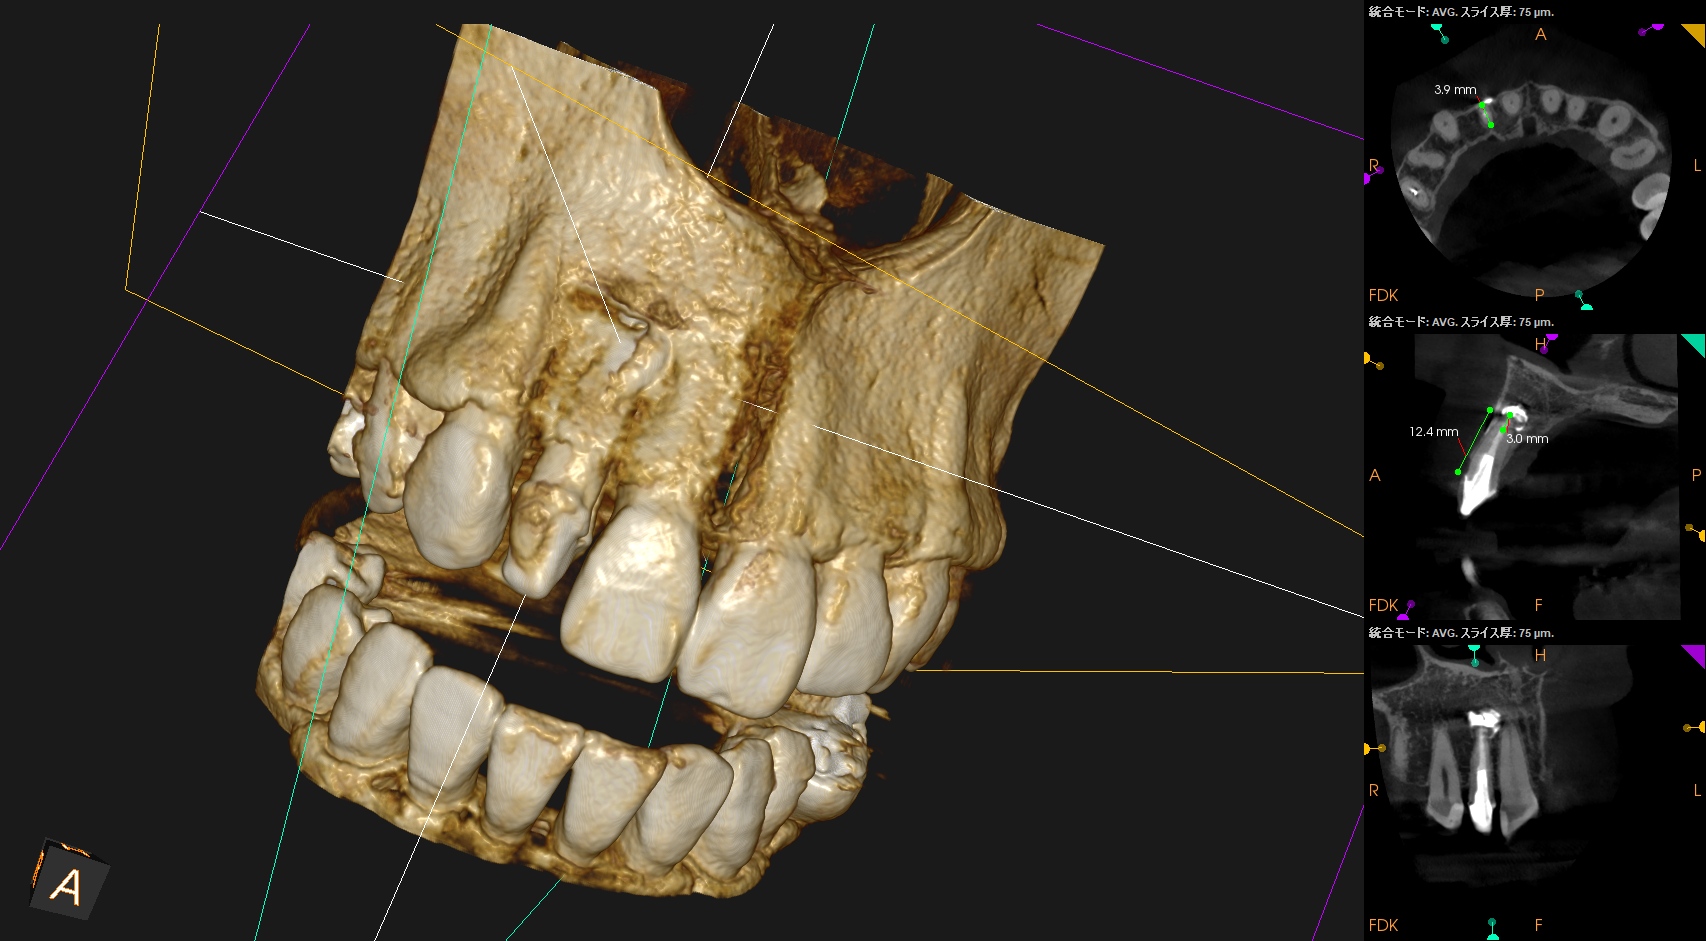

CBCT(2025.10.21)

Apexよりも12.5mm下方に#7のApexがあり、そこを3mm切断しようとすれば頬舌的に3.9mの切断が必要だ。

Apexの位置はクラウンマージン部より12.5mm下方だ。